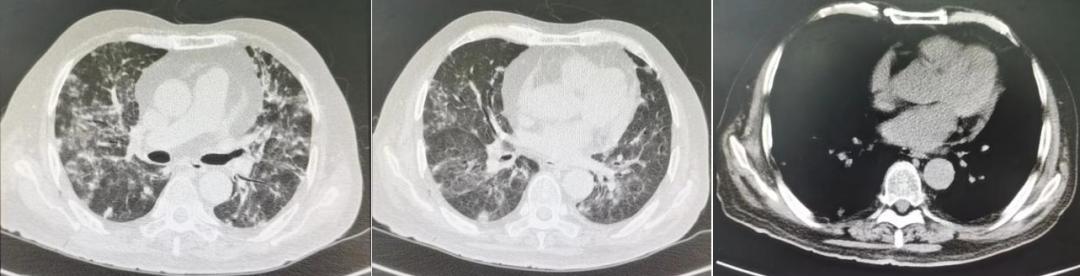

8月6日对患者进行胸部CT平扫示「双肺炎症」(见图1),留取痰培养(细菌、真菌、结核)后,于8月6日起予头孢唑肟(2g bid)联合莫西沙星(0.4g qd)经验性抗感染治疗。

图1:2022年8月6日患者的胸部CT平扫